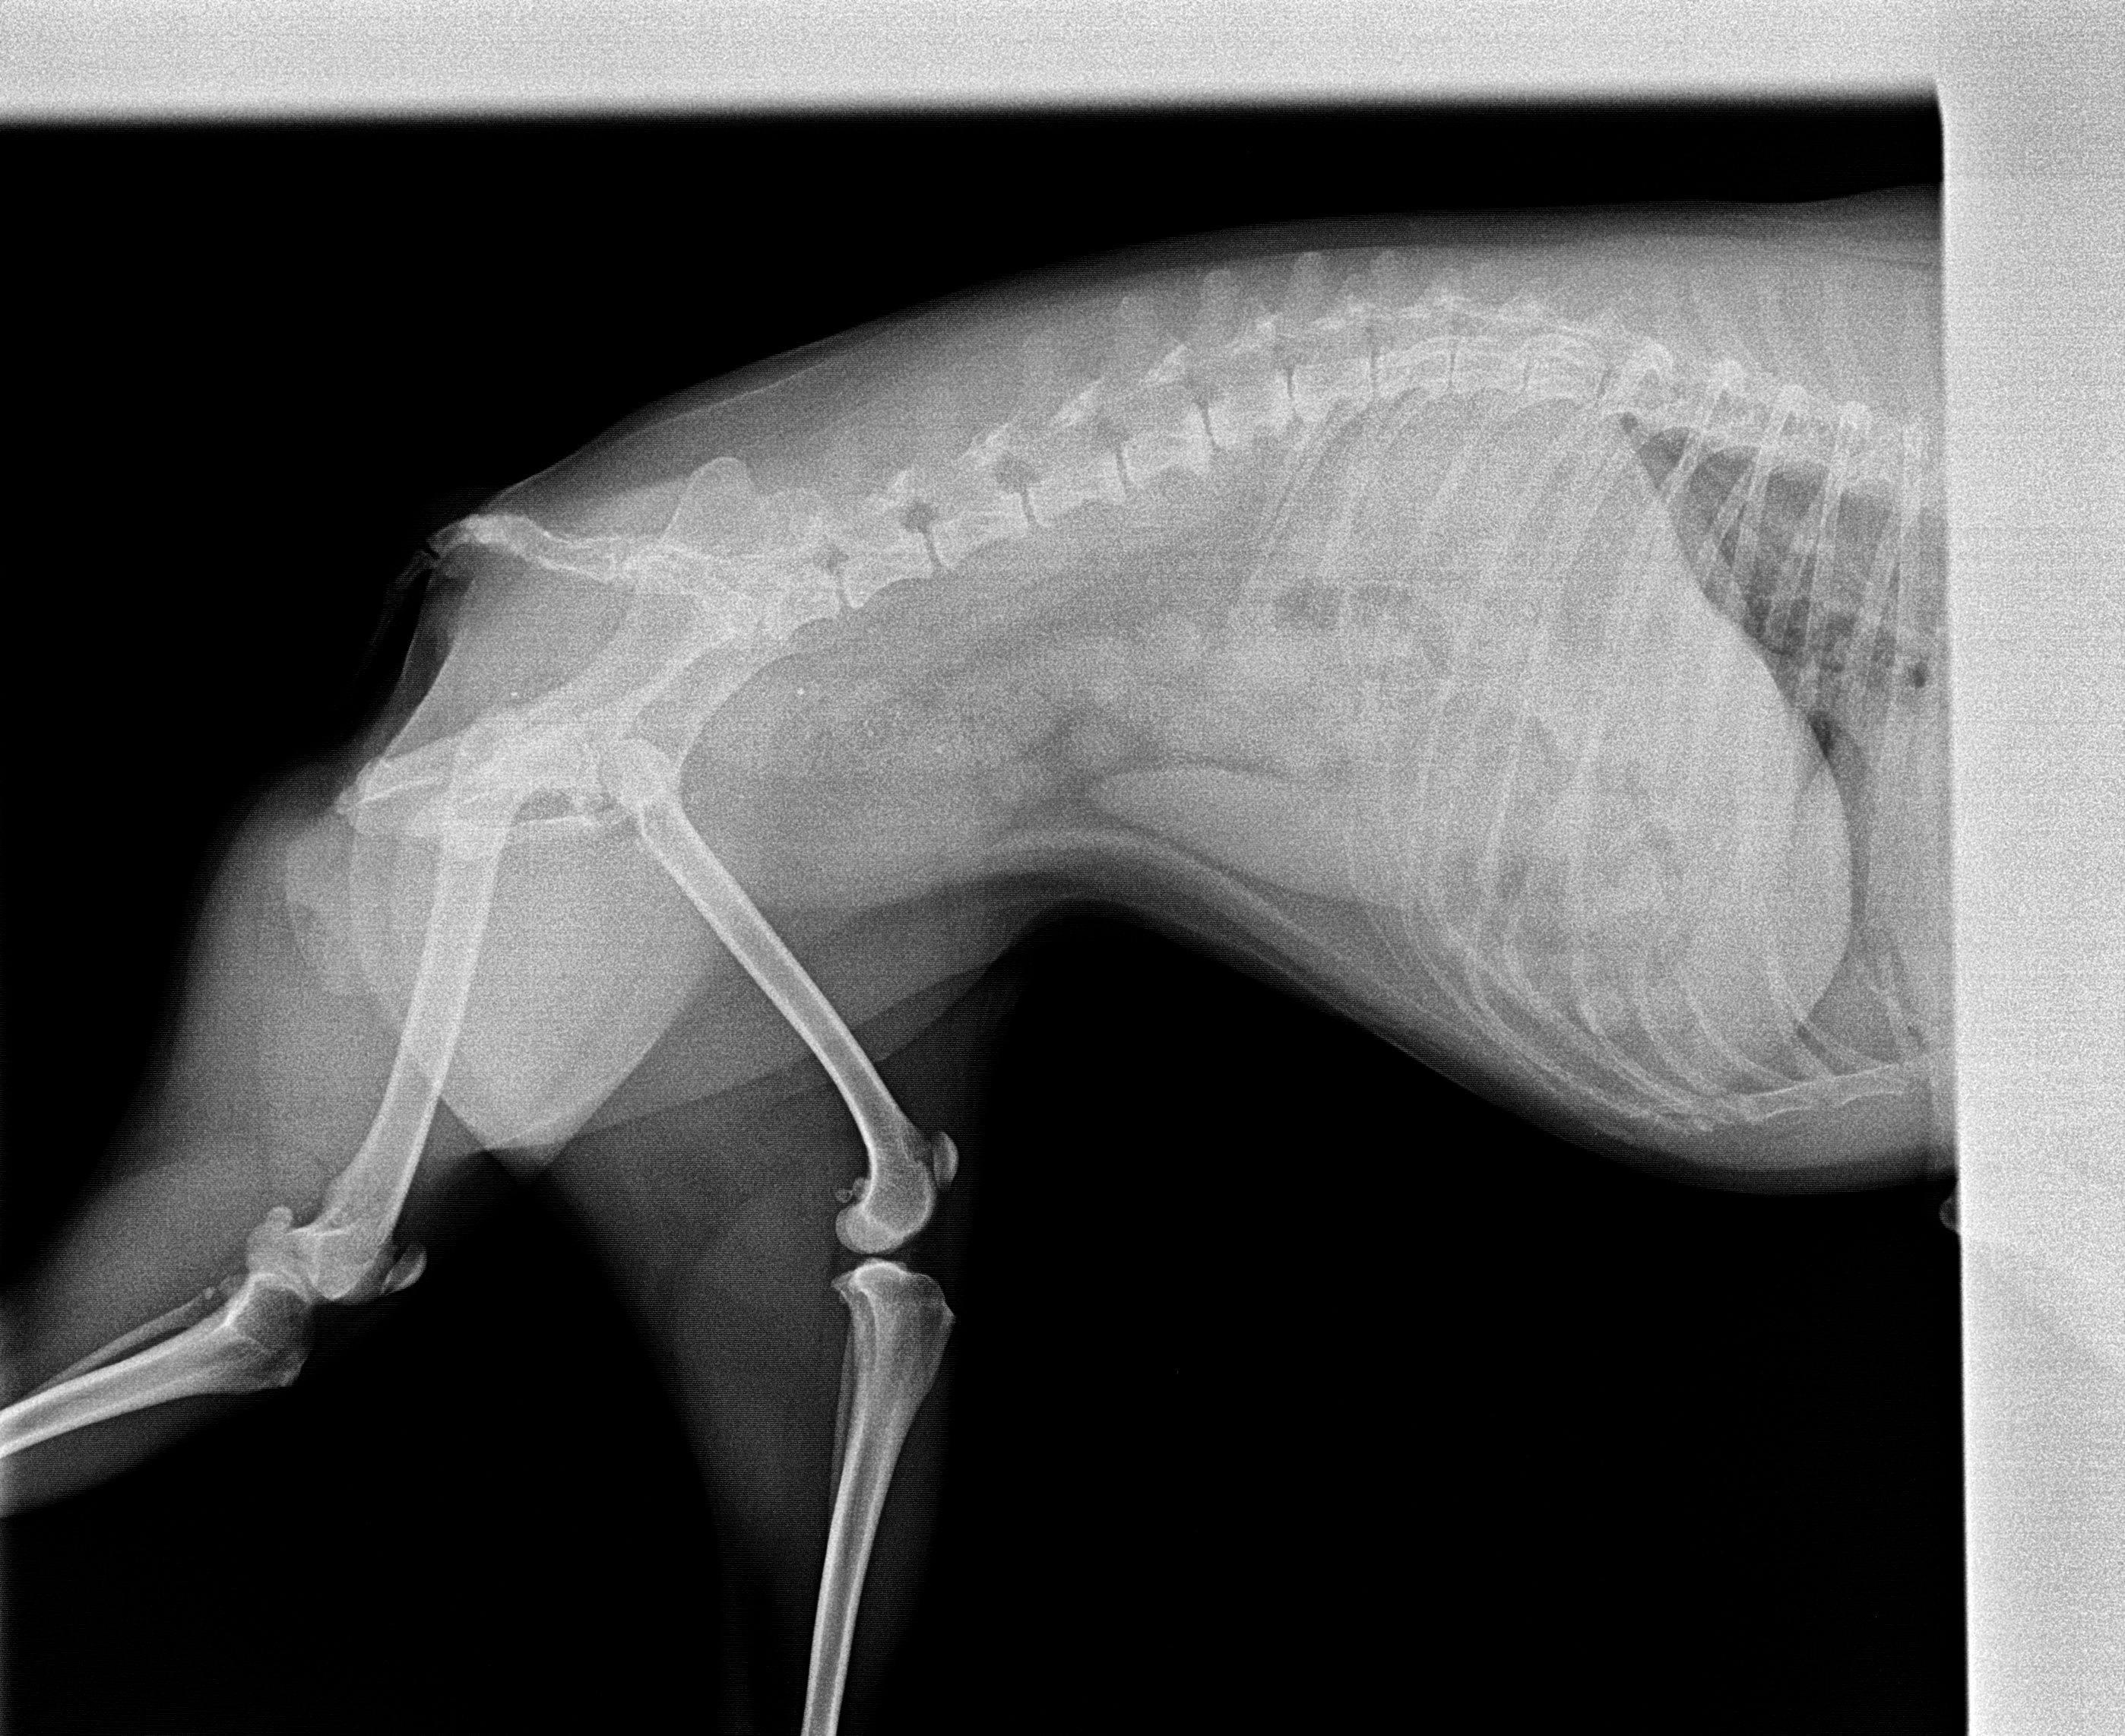

The images from the source dataset had issues and needed to be consolidated into a more usable framework. These issues were mostly due to inconsistencies in practices of radiographers and movement by the animals during radiography that resulted in radiographs with incomplete data, inconsistent image quality, such as varying contrast, brightness and positioning of point of interest or images that failed to meet the prerequisite conditions for this task. Examples of difficult data are shown in Fig. 5.